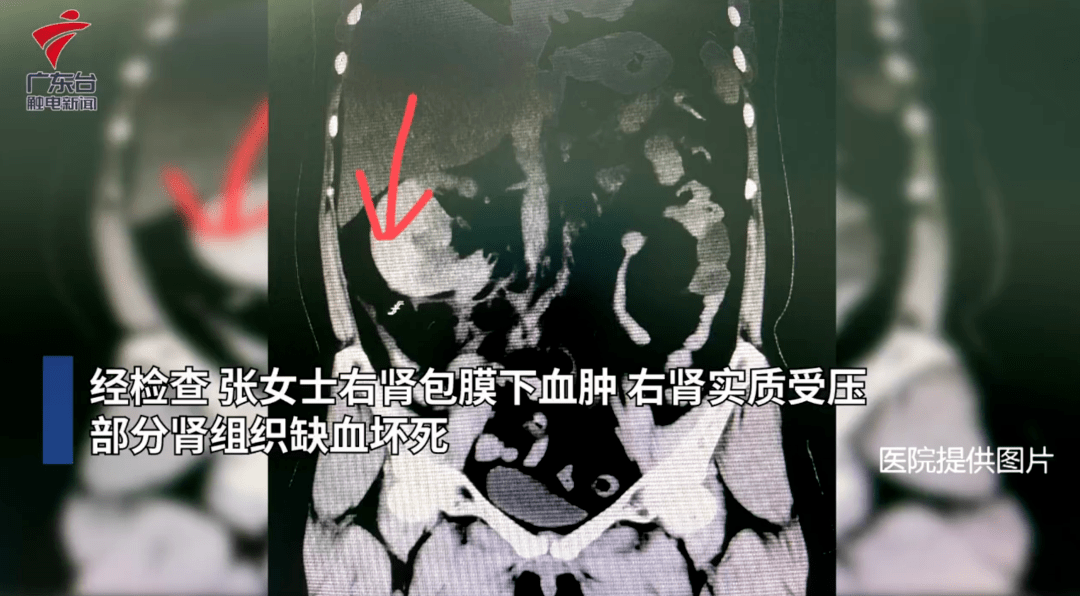

49岁的张女士为了减肥,把家用按摩仪调到最高档放在肚子上半小时,随后出现了高烧、剧痛等身体不适症状。经检查,张女士右肾包膜下血肿,右肾实质受压,部分肾组织缺血坏死。